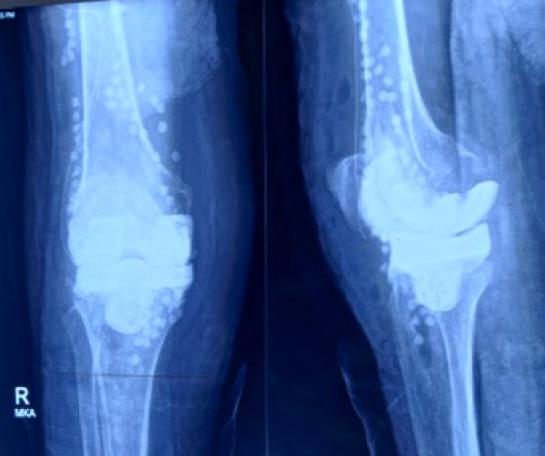

A few cases of periprosthetic infection by A. xylosoxidans have been reported outside India. A periprosthetic infection with A. xylosoxidans following a total knee arthroplasty is reported in a female.

印度以外地区已报道了几例木糖氧化无色杆菌引起的假体周围感染病例。本文报道了一名女性在全膝关节置换术后发生木糖氧化无色杆菌假体周围感染的病例。